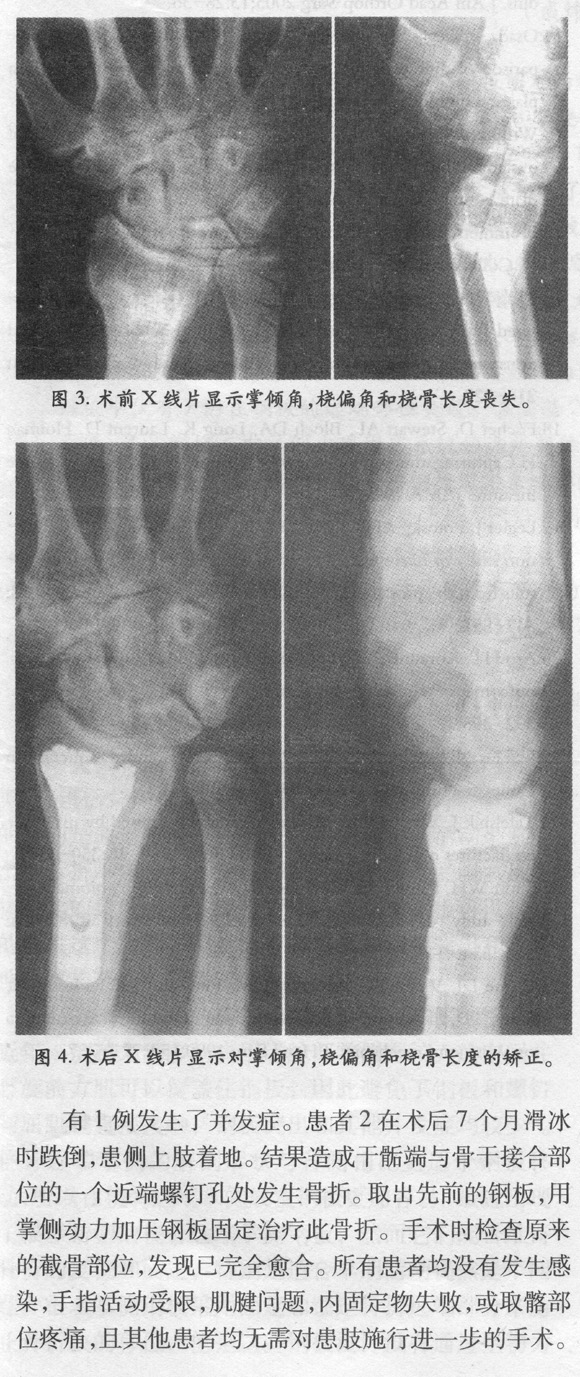

用掌侧角状钢板矫正桡骨远端背侧成角畸形愈合:病历系列报道 ... ... ...